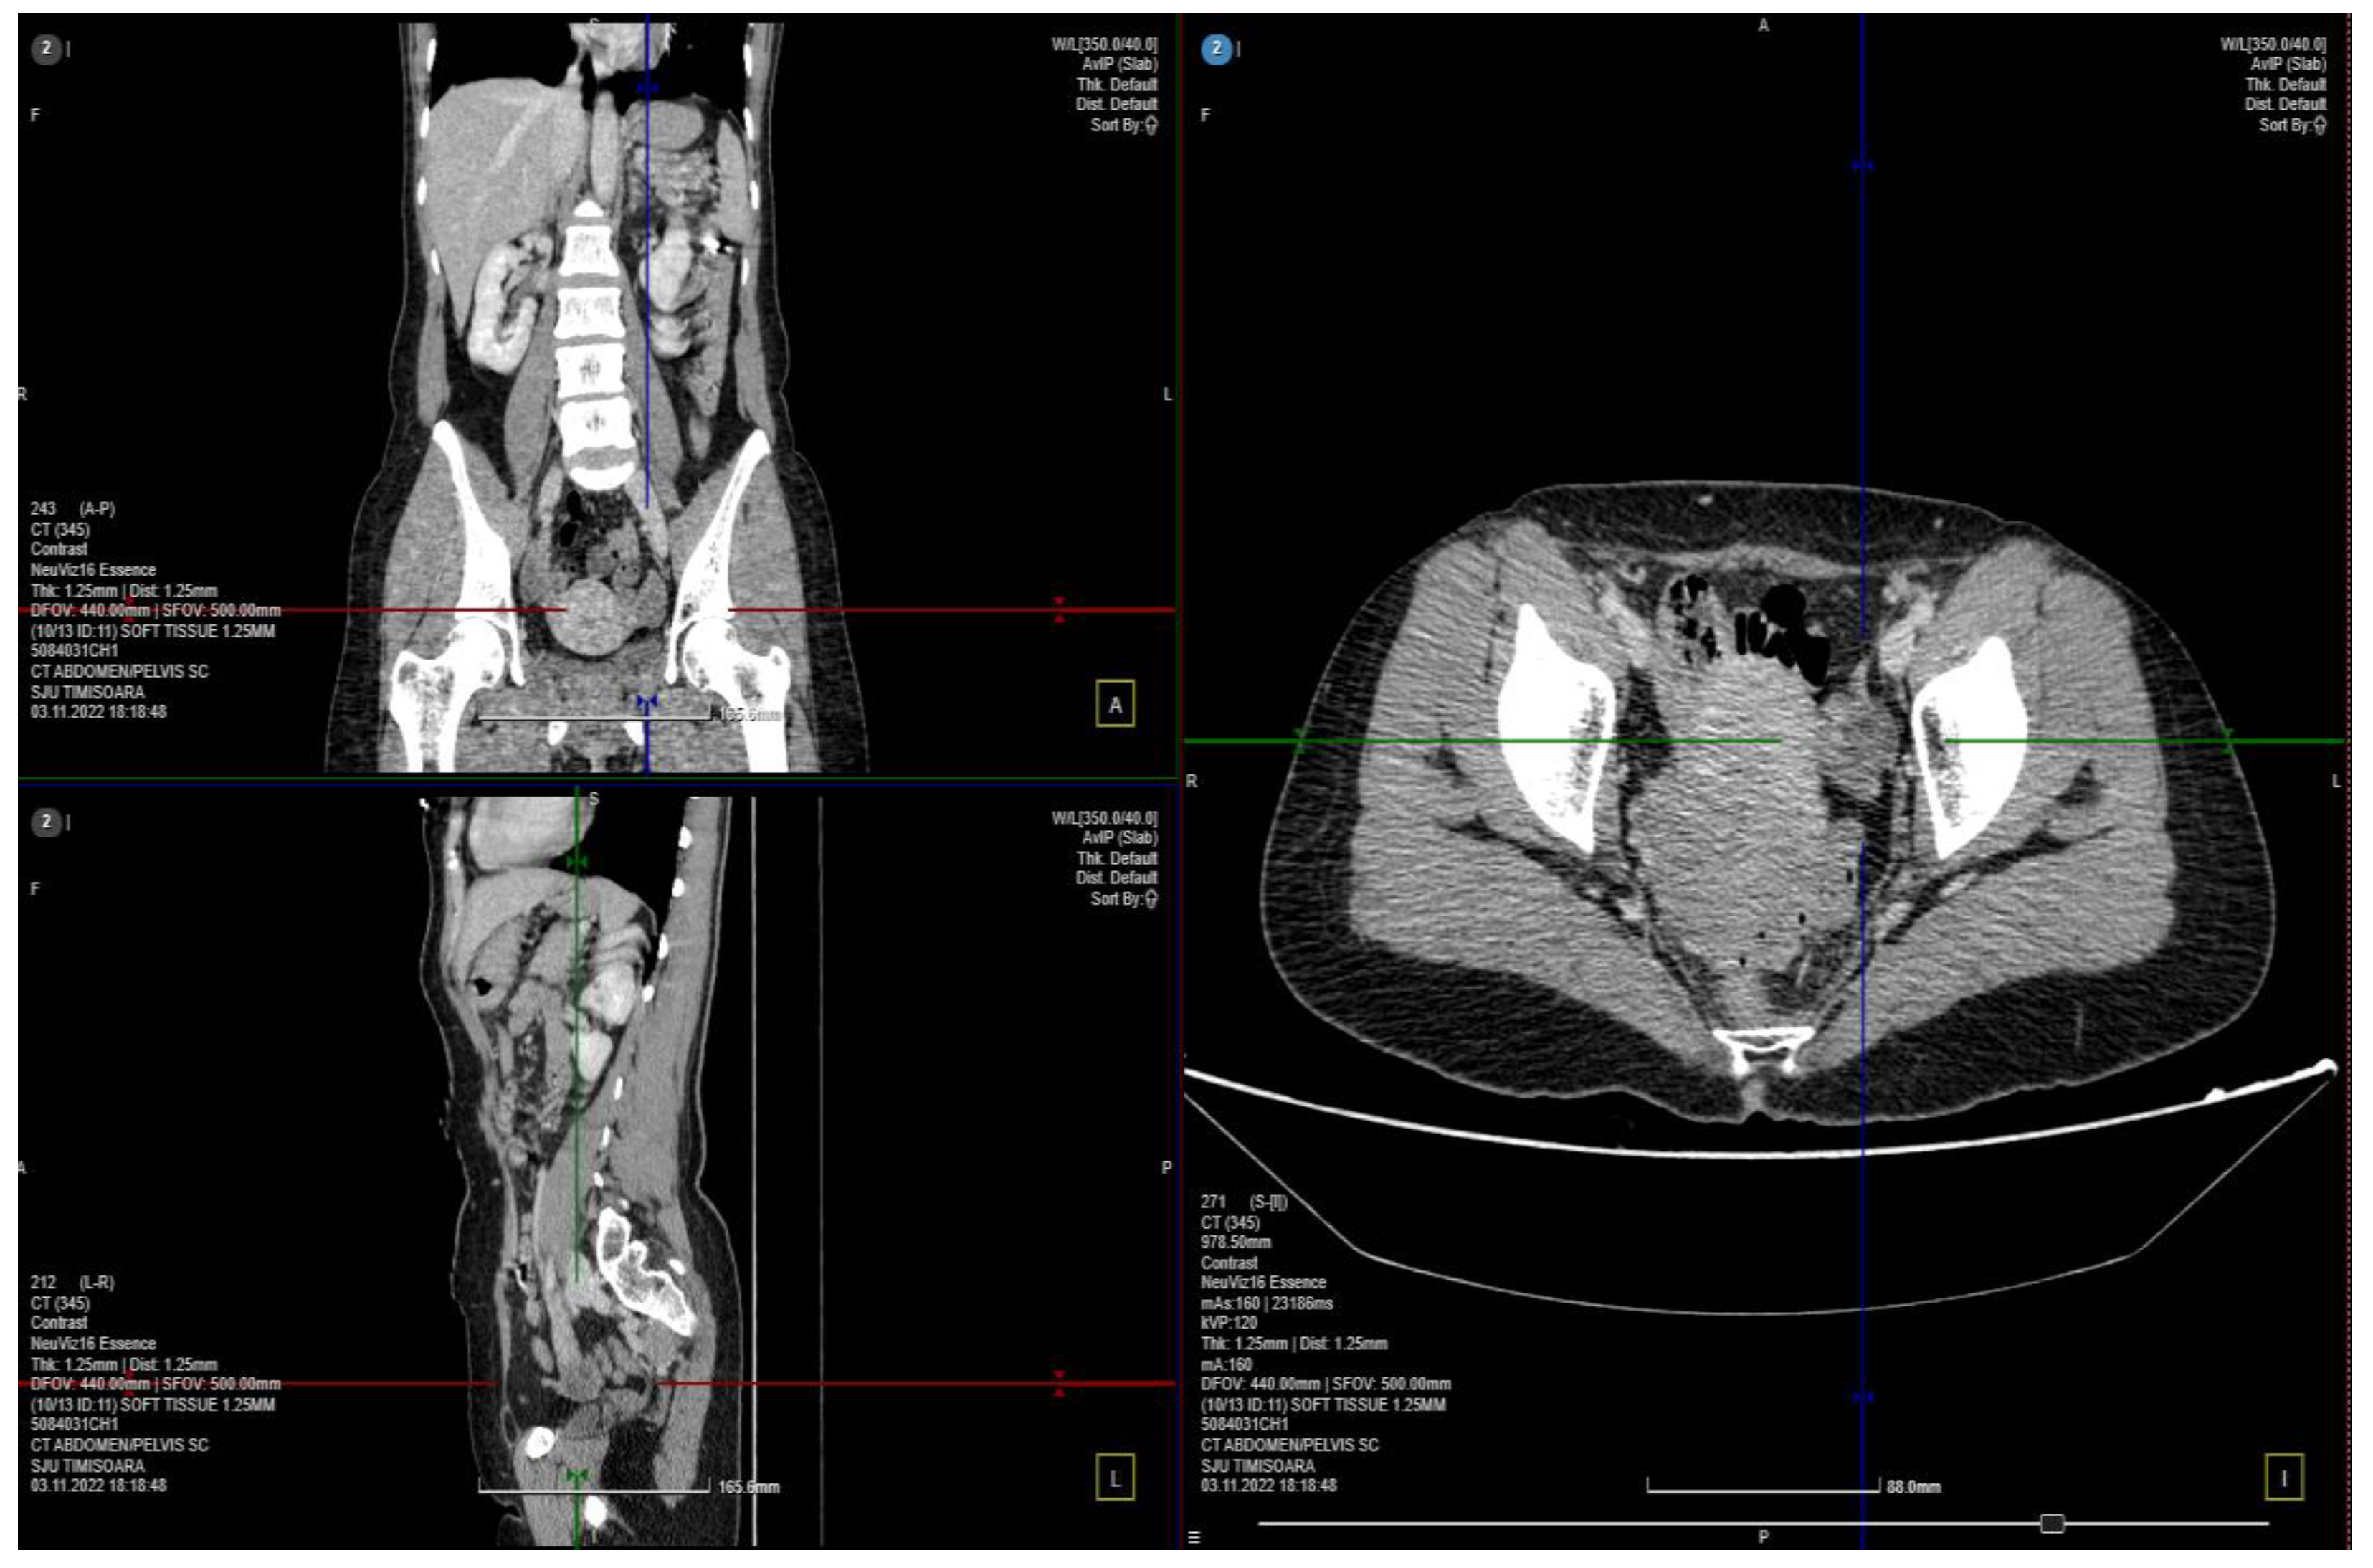

A computed tomography (CT) scan was performed, and a few images of the cystic characters on the left ovary were observed without signs of local complication (Figure 1). The parauterine vasculature was up to 5 mm in diameter, and the caliber is reserved for the examination of the patient in the supine position. No specific signs of an acute inflammatory pathology, such as appendicitis or diverticulitis, were noted. Uterus and adnexa are difficult to assess accurately through the use of current investigation–recommended correlation with gynecological (GYN) examination and completion using pelvic magnetic resonance imaging (MRI) with a contrast material.

Figure 1.

CT scan of the abdomen and pelvic 3 different plans: the coronal, sagittal and axial planes.